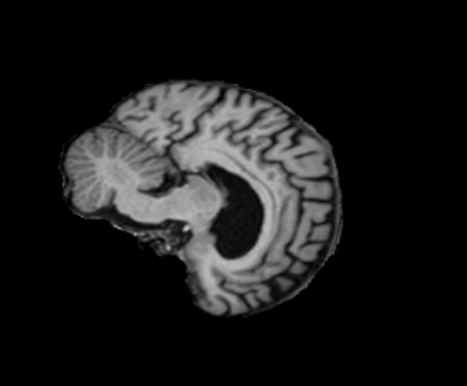

3.2.2 Robustness

In this experiment, we evaluate the robustness of Polaffini and the competing methods by computing a failure rate. We considered as potential outliers all cases for which the average Dice score over all regions after registration was below 0.34 (Z-score below -1.5, pooling Dices from all affine methods). All potential outliers were visually inspected to assess the reason behind the poor anatomical structure overlap score. All of them were clear failure cases, not just a residual misalignment to be expected after an affine registration. The failure counts for each method are reported in table 2. Almost all of the failure cases only occurred when registering with Flirt, mostly when subjects from the IXI dataset were involved. The most common failure type, showcased in Fig 6-a., consists of a local minimum where the frontal part of the moving brain is matched with the cerebellum of the reference one, a less frequent upside-down outcome is showcased in Fig 6-b. We suspect it is due to the fact that images from IXI have their axes ordered differently compared to the other two datasets and the template. However, since this information is contained in the header, it is unclear why Flirt could not handle the situation properly. Without the restriction of the angle search to , Flirt would give worse results (19 failure cases for subject-to-template and 61 for subject-to-subject). The only failure case using Anima for subject-to-subject is shown in Fig 6-c. For the rest of this section, we discard registrations if at least one of the methods has failed.

| reference | moving | moved | reference and moved | |

| a. | ukb_1154012-20252 | adni_AD-012-S-0720 | registered with Flirt | |

![]() |

|

| b. | ixi_165-HH-1589 | ukb_1145033-20252 | registered with Flirt | |

| c. | ixi_143-Guys-0785 | adni_MCI-003-S-6258 | registered with Anima-aff | |